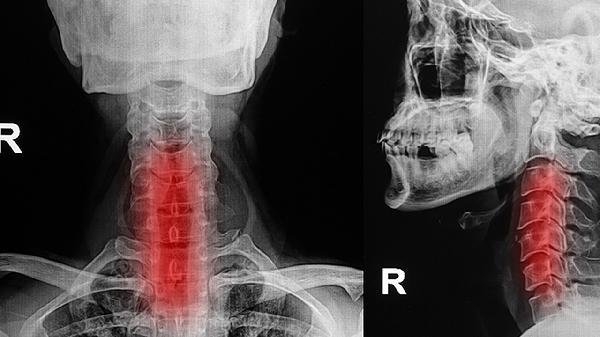

咽喉部CT或MRI检查能显示深层组织结构,用于评估肿瘤侵犯范围、淋巴结转移等情况。增强扫描可鉴别血管性病变,三维重建有助于手术规划。检查前需去除金属物品,增强检查需签署造影剂知情同意书,肾功能不全者需提前告知医生。